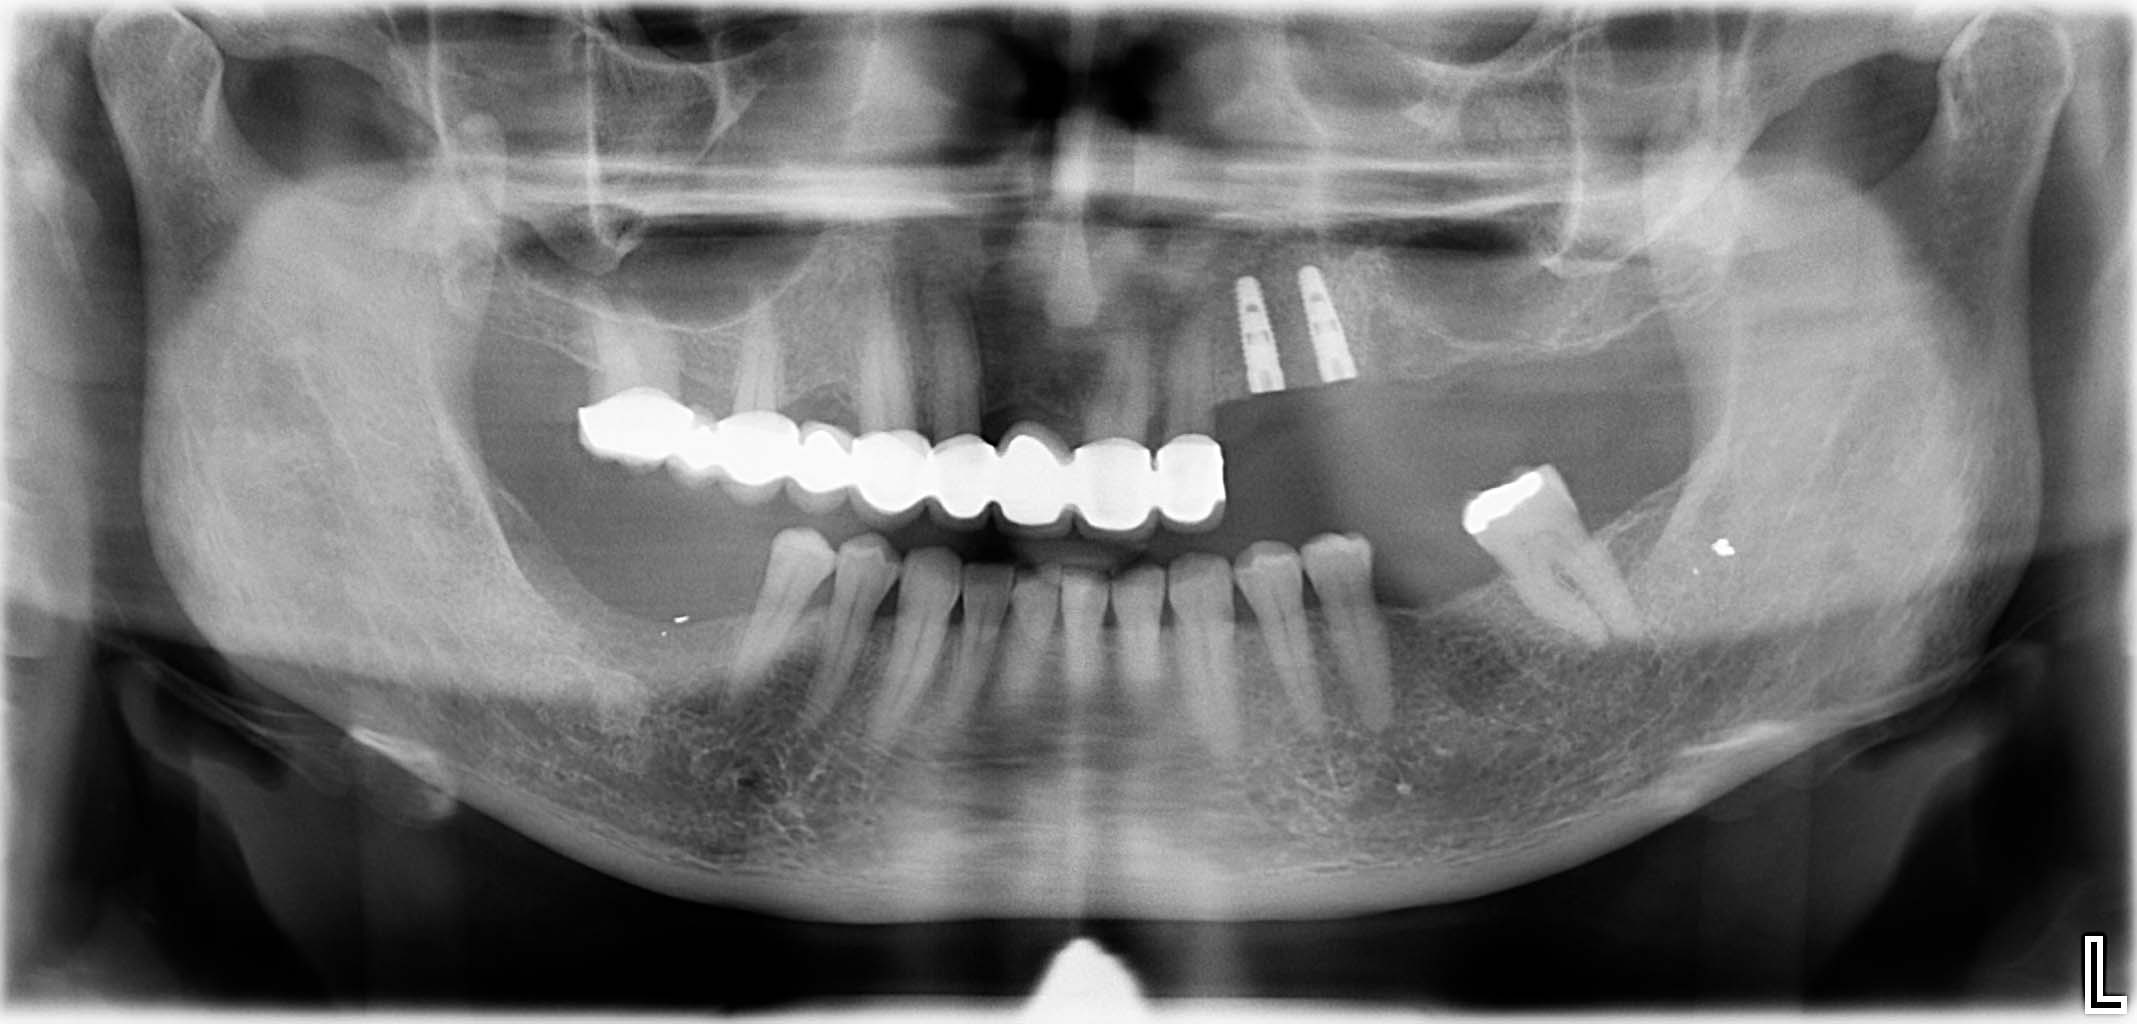

Erfolgreich implantierte Patientenfälle (klinische Fotos)